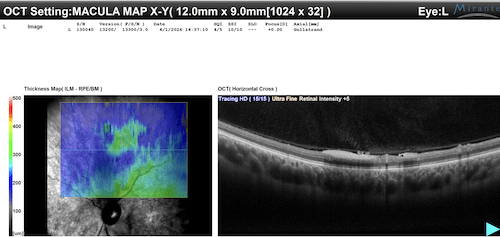

OCT Maculare

Le scansioni OCT a livello del polo posteriore OS documentano un quadro favorevole:

- Profilo foveale e depressione foveale sostanzialmente conservati.

- Assoluta assenza di edema maculare cistoide (CME) o di fluido sottoretinico (SRF).

- In corrispondenza dell’arcata superiore si nota una modesta componente superficiale/preretinica iperriflettente, coerente con il tessuto fibrovascolare osservato oftalmoscopicamente, priva tuttavia di significativa trazione sulla macula.

| OCT | Profilo maculare conservato. Assenza di fluido intra/sottoretinico. Materiale iperriflettente preretinico superiore. | Assenza di complicanze maculari (edema/trazione). Funzione visiva centrale preservata. |